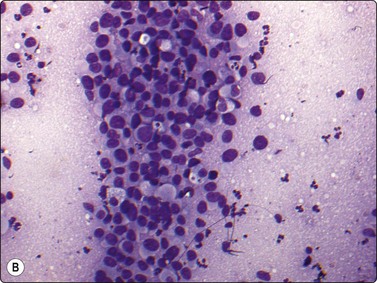

Malignant lymphoma

Over 90% of non-Hodgkin lymphomas in children are high-grade lymphomas.14 The most common types are T and B lymphoblastic, Burkitt and anaplastic large cell lymphoma while diffuse large B-cell lymphoma is less common.20 Lymphoblastic, Burkitt and diffuse large cell lymphomas in children can be mistaken for any other SRCTs on the basis of morphology alone. Within the paediatric population, each of these lymphomas has distinct clinical features which are important to recognize.71 Lymphoblastic lymphoma typically affects young teenage boys, and is a common cause of a mediastinal mass as well as peripheral, usually supradiaphragmatic, lymphadenopathy. Most of these are T-cell immunophenotype and positive for terminal deoxynucleotidyl transferase (TdT). Aspiration smears are highly cellular with a singly dispersed monotonous population of lymphoblasts with no evidence of true intercellular cohesiveness. The cells are twice the size of normal lymphocytes. Nuclei demonstrate finely granular chromatin with inconspicuous nucleoli, and only a thin rim of delicate cytoplasm (Fig. 17.12). Abundant lymphoglandular bodies are present in the background and serve as an important diagnostic clue of the lymphoid lesion. Neuroblastoma enters into the differential diagnosis as it can present as a primary mediastinal lesion. However, intercellular cohesion, nuclear molding, typical Homer-Wright rosettes and absence of lymphoglandular bodies favor the diagnosis of neuroblastoma.

image

Fig. 17.12 Lymphoblastic lymphoma

Highly cellular smears contain a monomorphic population of lymphoblasts with no true intracellular cohesiveness. The cells demonstrate uniform round nuclei with finely dispersed chromatin, inconspicuous nucleoli, and a thin rim of cytoplasm. Numerous lymphoglandular bodies are readily identifiable in the background.